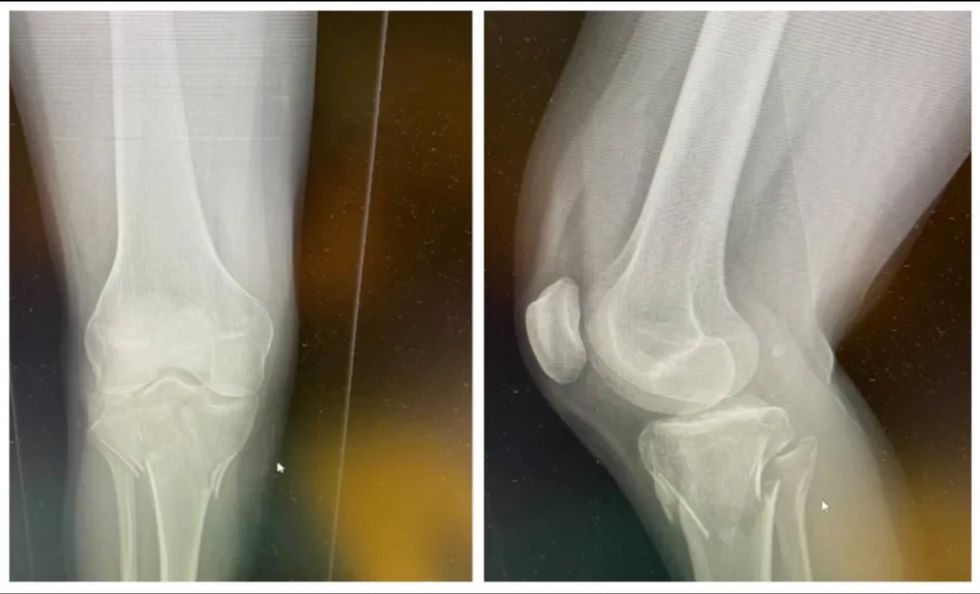

She needed surgery to repair a cracked tibia

Boudreau told Narcity that she had been in hospital since Sunday and was being scheduled for surgery to repair a cracked tibia on Monday afternoon.

The accident was painful but she was in good spirits: “First time on a motocross bike, and I ran into a concrete block," she said. "The head of the tibia cracked. I'm having the operation at around 1 p.m. today.”